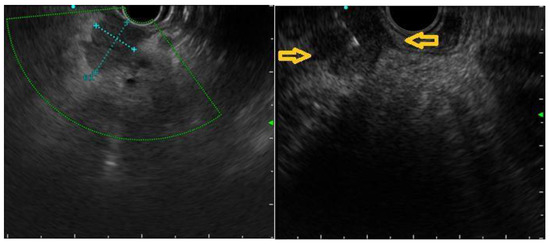

3.2. EUS Characteristics